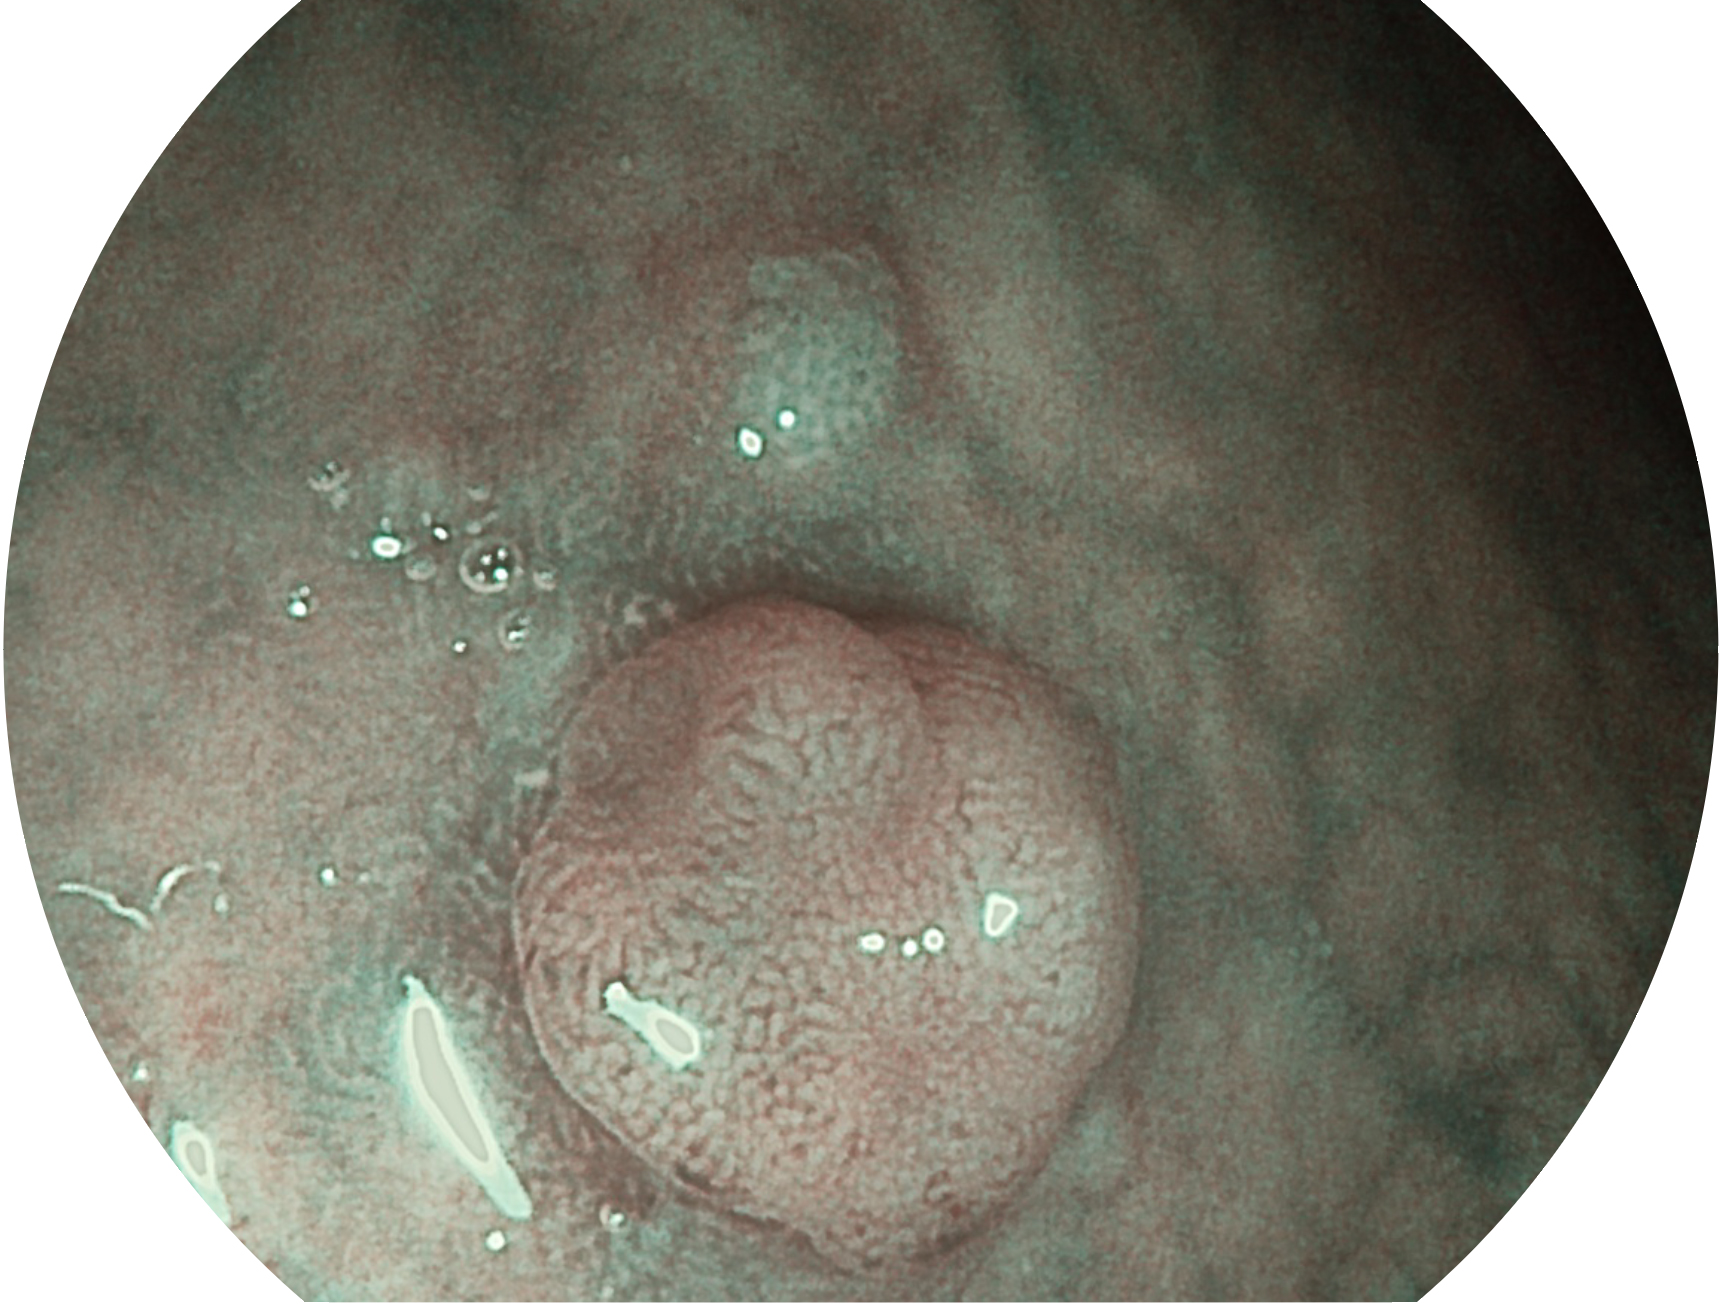

云顶集团官网新开发的内镜染色技术,主要是基于多波长LED 光源的开发,VLS-55Q 四波长LED 光源是由四个不同颜色的LED光按照相应照明模式所规定的特定发光比例进行合束后形成,合束后形成的照明光的光谱由红光、绿光、蓝光及蓝紫光这四个不同的波段范围构成。具有更高光谱自由度,通过光谱比例的控制,实现了聚谱成像技术,英文全称为“Spectral Focused Imaging, SFI”,缩写为“SFI”和光电复合染色成像技术,英文全称为“Versatile Intelligent Staining Technology, VIST”,缩写为“VIST”。